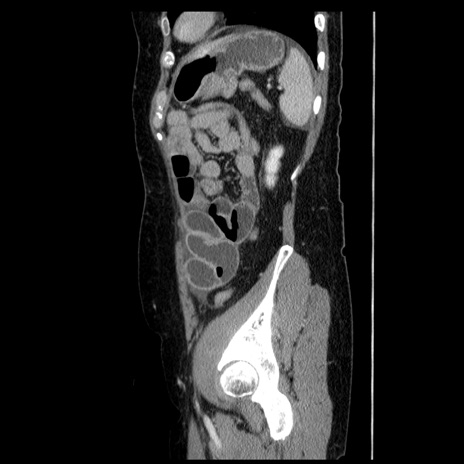

横断像

【症例】50歳代女性

【主訴】下腹部痛

【現病歴】本日朝より下痢2回あり。 昼食を食べた後、嘔吐3回、下腹部痛認め、症状軽快せず、当院救急搬送。

最終食事:本日昼(生ものなし)。 昨日の夜、刺身を食ぺたとのこと。周囲に同様の症状の者なし。普段、排便は毎日あるとのこと。

【既往歴】卵巣癌術後(8年前に当院で卵巣摘出)

【身体所見】 意識清明、腹部:平坦、腸蠕動音→、やや硬、下腹部自発痛・圧痛あり、反跳痛あり、筋性防御なし。

【データ】WBC 16000、CRP 0.01